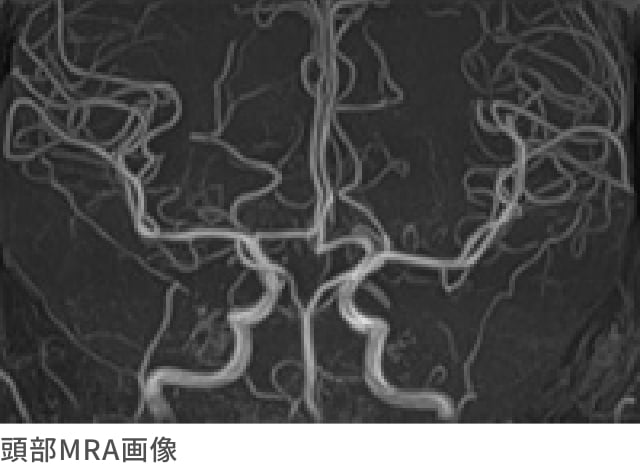

MRA検査とは

造影剤を使用せずに血管の画像を得るための検査です。

頭部MRA検査は、くも膜下出血の原因となる脳動脈瘤や血管の異常発見などに有効な検査です。